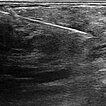

Um die Diagnose trotz der Hinweise auf ein infantiles Hämangiom klar zu sichern, bei differentem Verhalten der kutanen (fast rückgebildet) und der subkutanen Anteile (Wiedervergrößerung), wurde noch eine histopathologische Sicherung mittels Stanzbiopsie durchgeführt. Das Ultraschallbild zeigt die Biopsiepistolennadel innerhalb des Tumors am Oberarm.